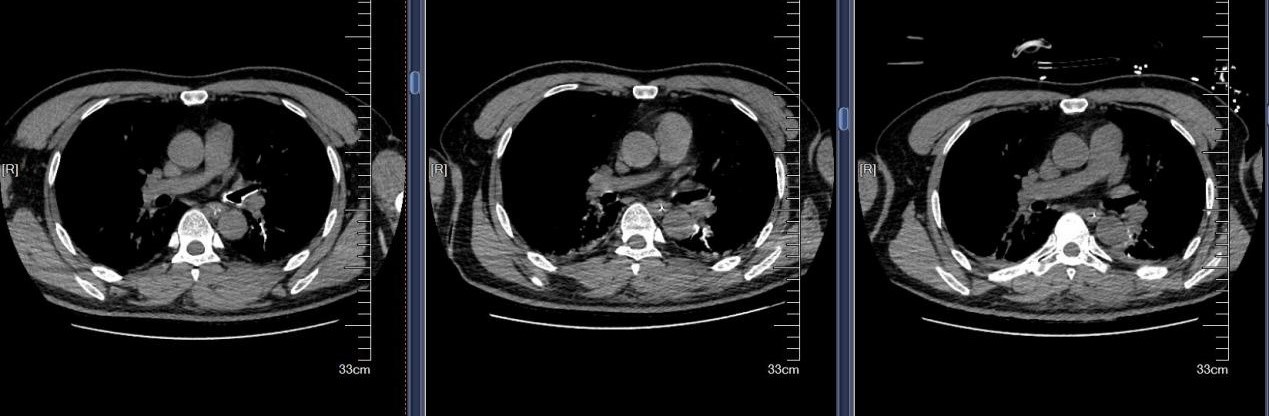

近日,苏州大学附属第四医院成功救治一例极其罕见的支气管异物危机案例。患者是一名48岁男性,因全身被水泥覆盖,伴有意识不清、呼吸困难等危急症状。紧急送医至我院后,CT检查发现其气管和双侧主支气管内充满大量高密度泥沙状异物,同时伴有多发肋骨骨折及腰椎骨折等严重外伤。面对如此复杂的病情,苏大附四院呼吸与危重症医学科蒋军红主任率领团队迅速制定了精准救治方案,成功挽救患者生命。

水泥作为化学性异物,除了造成机械性呼吸道阻塞,还会引发严重的化学性肺炎和呼吸衰竭。患者到院时已出现意识不清、呼吸困难等危重症状,气道清理成为抢救的首要目标。我院蒋军红主任凭借丰富的临床经验和技术优势,带领团队展开了一场与时间竞速的生命营救。

首次支气管镜清除手术:解决大块异物阻塞。因患者颈部有损伤,未行硬镜置入,在麻醉手术科的密切配合下,为患者经口插入8.5号气管插管,接呼吸机辅助通气,建立稳定的呼吸通道。随后,气管镜顺利进镜,发现气管及左主支气管内充满泥沙样分泌物、黄脓痰及块状异物。随后,实行精准操作:用吸引器清除泥沙样物质及黄脓痰;使用活检钳分次取出左下叶大块石状异物,并配合取石网篮清理;刷检带出细小碎石,并进行多部位生理盐水灌洗,最大限度清除可见异物。